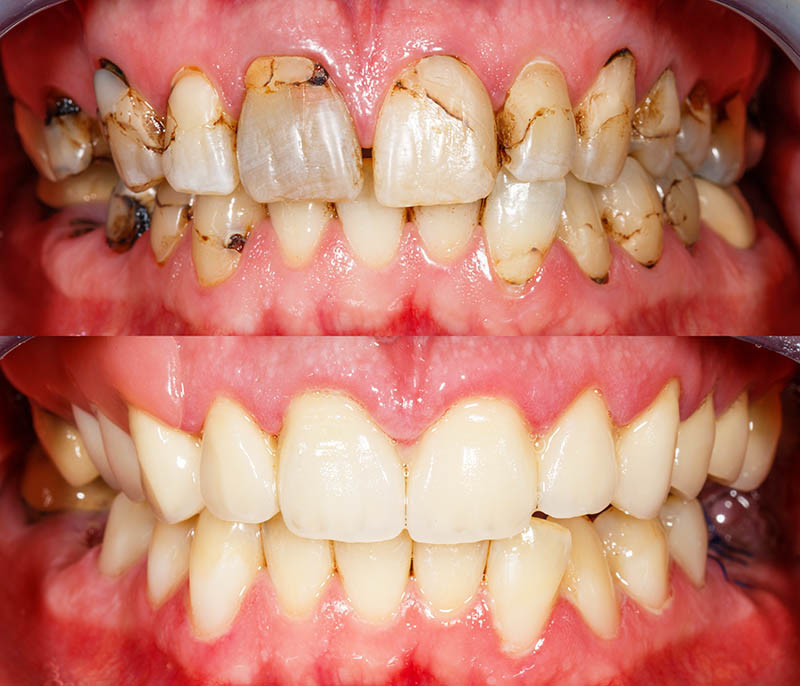

A rotten tooth is one that is severely decayed. The decay, also known as dental caries or a tooth cavity, begins with the breakdown of the tooth enamel. Plaque builds up and combines with bacteria to break down the enamel. Once the enamel has broken down, cavities develop. If you fail to treat your cavities, they will get worse. Dental caries is an open invitation to bacteria to further invade your teeth and beyond.

Dental caries results from a combination of not taking care of your teeth, the foods you eat, and in some cases, drugs of abuse or even legally prescribed medications. Foods that are high in sugar or starch are known to aid in breaking down tooth enamel. If you consume a lot of sugary drinks, the deterioration of enamel is accelerated. The presence of naturally occurring bacteria also accelerates this process. The bacteria and food build up and cause an acid that attacks the enamel accelerating the breakdown.

Visually, you might first notice discoloration as the enamel deteriorates followed by tiny holes in your teeth. You will also see dark spots as the decay becomes more apparent. As the decay gets worse, the toothaches will become unbearable, your teeth can crack, pieces of your teeth can break off, or a tooth can completely break at the gum line. You will start having trouble eating and may lose weight. It is possible you will lose important nutrients that are critical to your health. The symptoms of a rotten tooth will grow more severe as time goes by. You are more likely to notice this kind of symptom in a rotten back tooth or rotten bottom teeth. In comparison, rotten front teeth are relatively rare.

Decay that occurs on either your back teeth or your bottom teeth is treated with traditional fillings and crowns. It is more common for your back teeth to decay because they are harder to reach and may not get the care that your front teeth do when you brush and floss. No matter what stage of decay, you will notice a difference in your rotted teeth before and after treatment. With several options available, your rotten teeth do not need to be considered permanently damaged. The rotten teeth treatment options for each stage of decay are:

Advanced Stage Treatment Options

If your tooth decay is in the advanced stage, your dentist can still easily restore the permanently damaged tooth. Cavities are visible to the naked eye at this stage of decay. Using a dental drill, the decayed areas are removed from the tooth. The empty spaces are then filled in with either porcelain, composite resin that is colored to match your tooth or an amalgam composed of various metals and porcelain. If the decay has weakened the tooth, your dentist will remove your natural crown and a customized replacement crown may be made to order. Crowns are made of either porcelain, gold, or a metal-porcelain combination. The custom crown will replace the natural crown on your tooth and will be cemented into place. It is not uncommon to have a rotten tooth under crown.